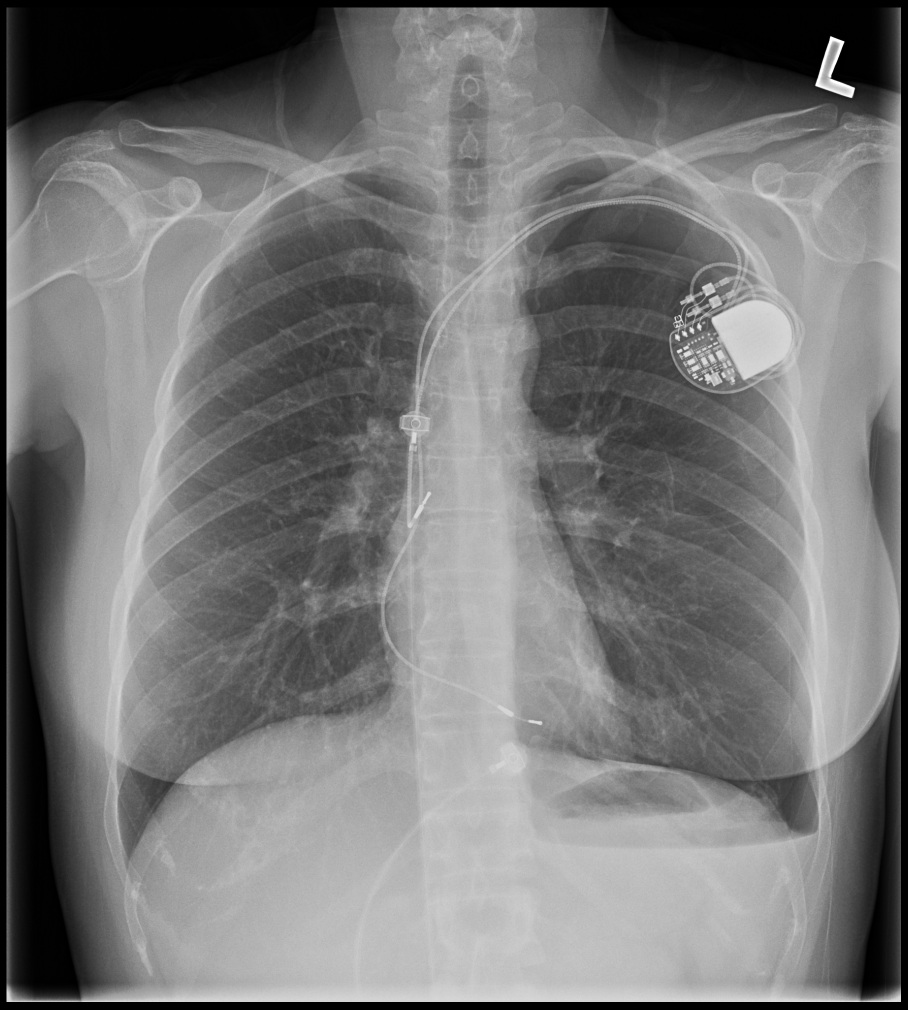

• Chest X ray after 4-6 hours

Post procedure CXR

pneumothorax_post_ppm.jpg